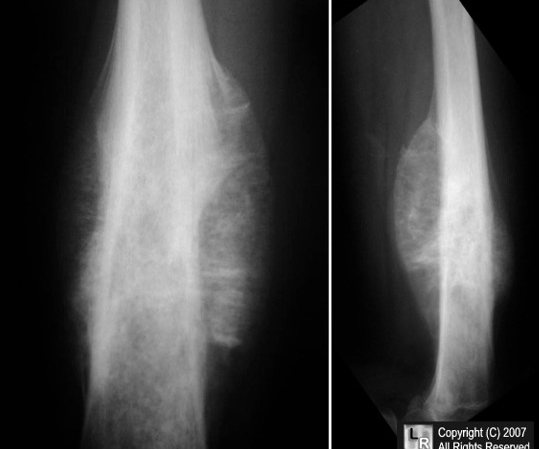

Blount:

A few children with bowlegs, however, continue to progress and worsen, and in some cases the bowing is unilateral. This is termed Blount disease and is characterized by an abnormality in the medial aspect of the proximal tibial epiphysis.

Labs: Radiographically there is a prominent step abnormality with beaking at the proximal tibial epiphysis.

Treatment: Aggressive treatment is essential, as the disease can be rapidly progressive and lead to permanent growth disturbances. Bracing can be effective up to the age of 3; later correction may require surgery. Blount disease can occur in several forms: infantile (ages 1-3 years), juvenile (ages 4-10 years), and adolescent (age 11 years and older). Clinically, the findings are the same; in the adolescent group, radiograph findings are less prominent.